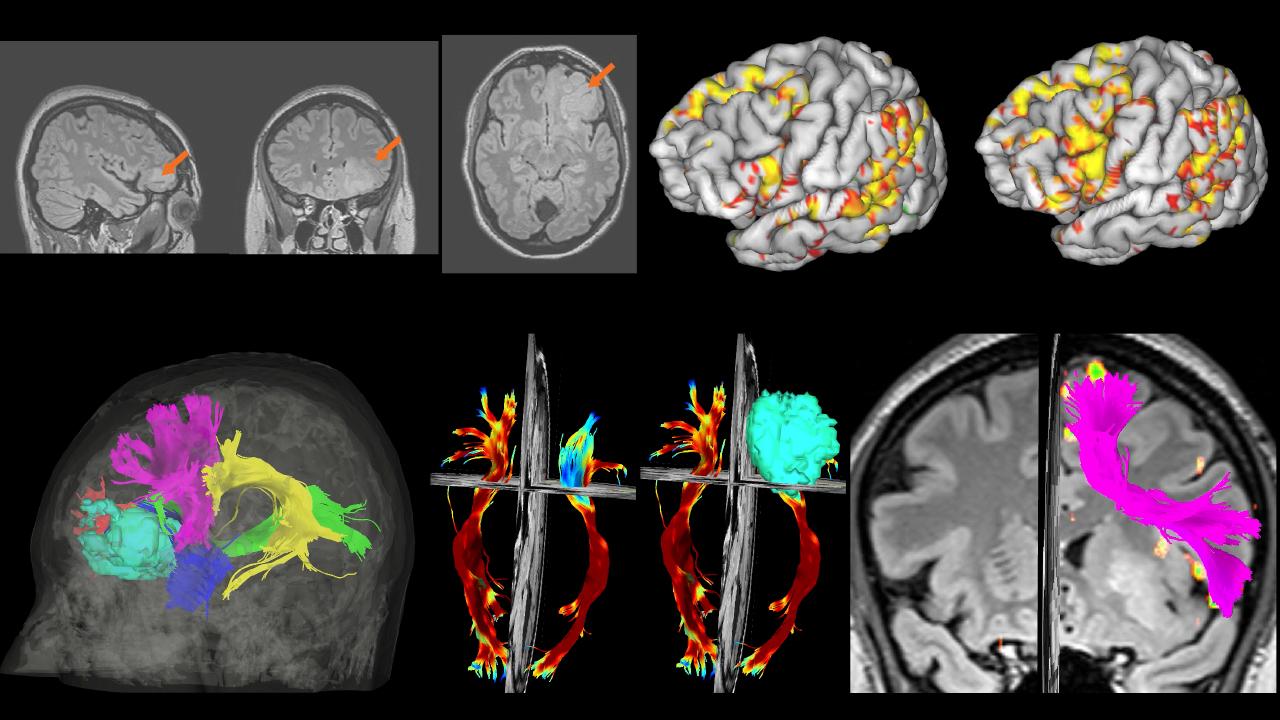

Fig 1: T2-FLAIR images of a patient with low grade glioma in the orbitofrontal area (white arrows). This patient performed 7 functional (fMRI) tasks in Arabic, only 2 tasks are shown (auditory questions, and a visual sentence completion task). The hot colors denote activations in the main language areas such as the pars triangularis/orbitalis, the posterior superior temporal gyrus, and dorsal and ventral premotor cortexes. Fiber tractography was also used to map the structural connectome and identify the white matter bundles that are critical for language. Shown in Fig. 1 fiber tractography overlaid on the tumor model (light blue), the arcuate fasciculus (yellow), the inferior fronto-occipital fasciculus (green), and the frontal aslant tract (purple).